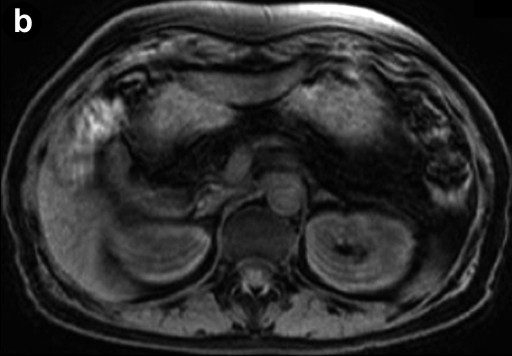

An esophagogastroduodenoscopy showed normal findings. Diseases such as reflux esophagitis and gastric ulcer were not observed. Ultrasonography (Figure 1) revealed a markedly heterogeneous pancreatic parenchyma demarcated from the neighboring tissues. The main pancreatic duct was not narrowed or dilated, and no tumor was detected. A CT image is shown in Figure 2. Plain CT (Figure 2a) revealed that the density of the pancreatic parenchyma had uniformly decreased to the same level as that of the surrounding fatty tissue. Contrast-enhanced CT (Figure 2b) revealed that the entire pancreatic parenchyma was absent and only a contrast-enhancing net-like shadow was visible. The magnetic resonance imaging (MRI) image is shown in Figure 3. The T1-weighted image could confirm that the entire pancreas was completely absent on T1-weighted images (fat suppression) (Figure 3). Endoscopic retrograde cholangiopancreatography (ERCP; Figure 4) showed no anomalous arrangement of the pancreaticobiliary ducts or pancreatic duct anomaly. Furthermore, obstruction, narrowing or dilatation of the main pancreatic duct was not observed. The branches of the pancreatic ducts appeared normal on the ERCP image. No abnormalities were observed in the bile duct.

Figure 3. Magnetic resonance imaging. a. T1-weighted image. b. T1-weighted image (fat suppression): the entire pancreas is completely absent. |